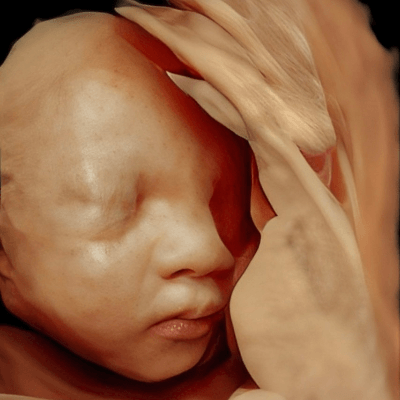

A 41-year-old secundigravida with a non-contributive medical history was referred for evaluation due to abnormal findings on a routine fetal ultrasound. Gestational age based on fetal biometry was estimated at 22 weeks.

We present a case of Campomelic Dysplasia.

Ultrasound revealed a single live fetus with 46,XY karyotype. Biometric measurements demonstrated discrepancies with the femur and tibia length lagging significantly at 19 weeks and notable shortening and bowing of the femur, tibia, and fibula. The findings were consistent with skeletal dysplasia.

Structural anomalies were observed in multiple organ systems. The fetal skeleton showed hypoplastic iliac bones, rib deformities, hypoplastic scapulae, and excessive cervical spine lordosis. The fetal hands exhibited abnormal alignment of the fingers with restricted movement, and both feet were clubbed. Subcutaneous edema was noted over the forehead and occiput with a small cystic hygroma, along with increased nuchal fold thickness at 5.6mm, indicative of soft tissue edema. Additional abnormalities included mild pyelectasis. The fetal stomach appeared nearly empty, likely reflecting impaired swallowing or associated anomalies. Polyhydramnios was also noted. External male genitalia appeared normal. Cardiac evaluation revealed multiple echogenic foci within the left ventricle and an atrioventricular septal defect. While the heart's overall structure and function were otherwise normal, these findings added to the overall suspicion of a syndromic condition.

Based on the combination of skeletal anomalies, soft tissue findings, and associated organ abnormalities, the ultrasound findings were highly suggestive of campomelic dysplasia. It was therefore recommended that the patient undergo genetic counseling and molecular testing, specifically for SOX9 mutations to confirm the diagnosis. Given the likely association with tracheal cartilage weakness, severe respiratory compromise was anticipated postnatally, with a high likelihood of requiring mechanical ventilation. The patient was advised to deliver at a tertiary care center equipped with neonatal intensive care and specialized support to address anticipated respiratory challenges and other complications. Unfortunately, the neonate died due to complications of assisted ventilation in the first weeks of life.